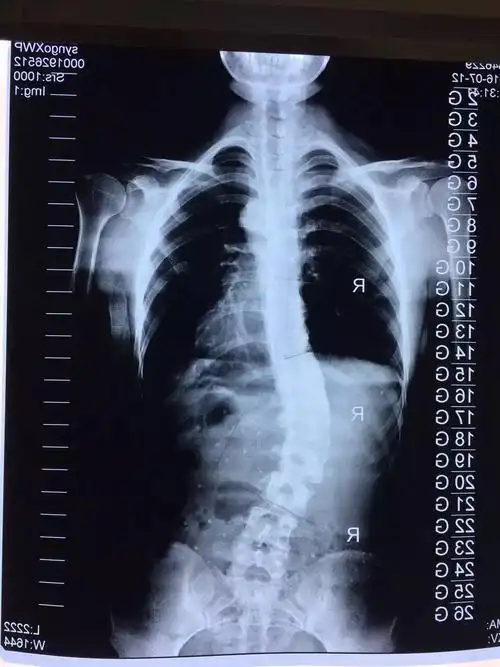

青少年特发性脊柱侧弯之lenke5型

脊柱侧弯11岁女孩cobb角度45度

小巧,隐蔽,高矫正率的支具帮助少女摆脱脊柱侧弯手术

各位老师看一下片子是否有脊柱侧弯

其他回答 怎么有明显的脊柱侧弯?